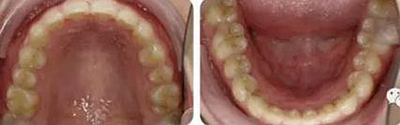

治療23個月結(jié)束??梢妰蓚?cè)尖磨牙達到中性關(guān)系,上下牙列排齊整平,前牙覆合覆蓋正常,中線齊。

曲斷可見牙根基本平行。

術(shù)前術(shù)后描記圖顯示上牙列整體遠移有效,表現(xiàn)為磨牙遠移及上前牙內(nèi)收(黑色術(shù)前,紅色術(shù)后)。